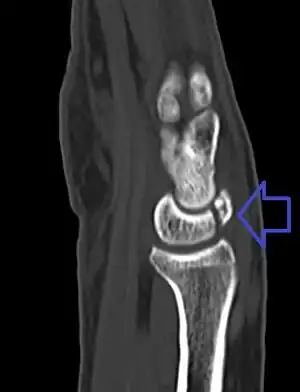

| A lunate fracture as seen on CT scan of the wrist | |

The cause is often a fall onto the hand.[2] Types include palmar pole, distal pole, transverse, osteochondral, and transarticular body.[1] Diagnosis is typically confirmed by plain X-rays, CT scan, bone scan, or MRI.[1] Other conditions that may appear similar include Kienböck disease and congenitally bipartite lunate.[1]